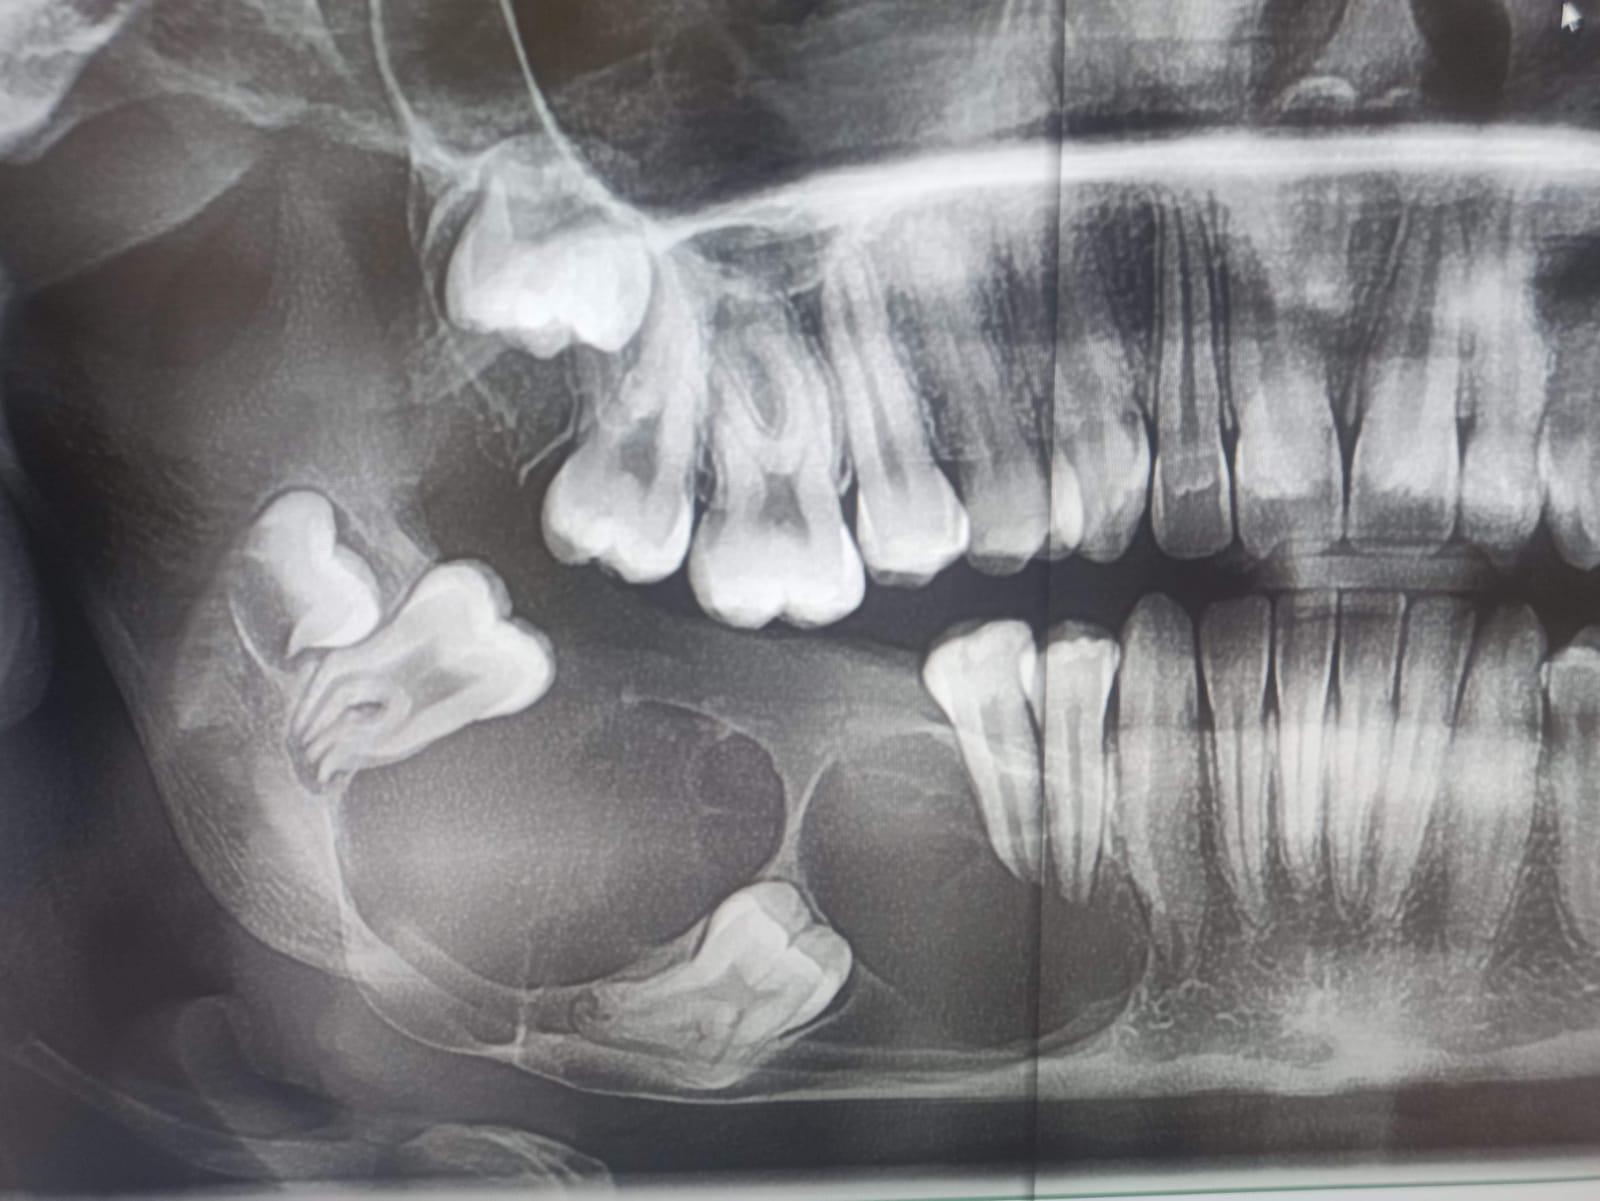

Pacjentka lat 15, zgłosiła się do poradni chirurgii szczękowo - twarzowej Szpitala Specjalistycznego im. L. Rydygiera w Krakowie z powodu rozległego guza trzonu, kąta i gałęzi żuchwy po stronie prawej. Na wykonanym zdjęciu ortopantomograficznym (OPG) uwidoczniono rozległy wielokomorowy ubytek kości żuchwy z całkowicie zatrzymanym zębem 46 w jego świetle oraz zepchnięciem zębów 47,48 w kierunku gałęzi żuchwy (Fig. 1.). W badaniu tomografii komputerowej uwidoczniono guz zniekształcający kość żuchwy po stronie prawej z jej rozdęciem i niszczeniem blaszki korowej od strony zewnętrznej oraz wewnętrznej (Fig. 2.). Wynik badania histopatologicznego pobranych wycinków z guza potwierdził rozpoznanie szkliwiaka (typ pęcherzykowo-akantomatyczny).

Fig.1. Zdjęcie OPG 15-letniej chorej – charakterystyczny obraz radiologiczny szkliwiaka w zakresie trzonu oraz kąta żuchwy po stronie prawej z całkowicie zatrzymanym zębem 46, powodujący przemieszczenie zębów 47,48 w kierunku gałęzi żuchwy